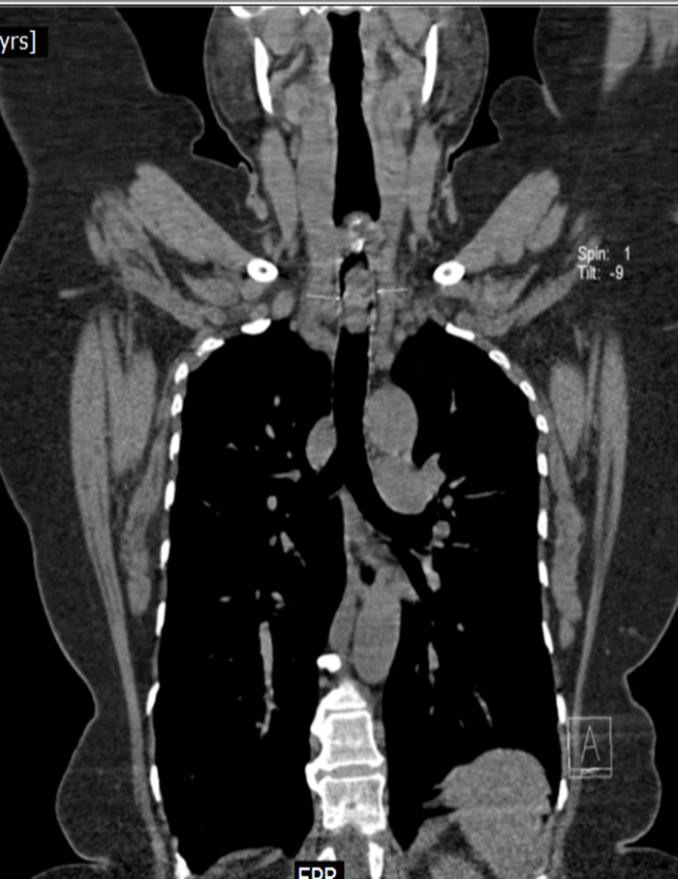

Contrast enhanced computed tomography (CECT) of neck and thorax reported intraluminal mildly enhancing polypoidal mass lesion measuring 2.58 x 1.54 x 1.51 cm (Cc X AP X Tr) in the upper trachea at the level of C6, C7 vertebral body. Significant luminal compromise was noted at the level of the mass lesion. Rest of the lung parenchyma was unremarkable. Flexible bronchoscopy examination revealed a large polyploidal growth approximately 3 cm from the vocal cords. The growth was moving with respiration and causing critical airway narrowing at the upper trachea (approximately 80%).

CECT at presentation: Intraluminal mass lesion in the upper trachea

CECT at presentation